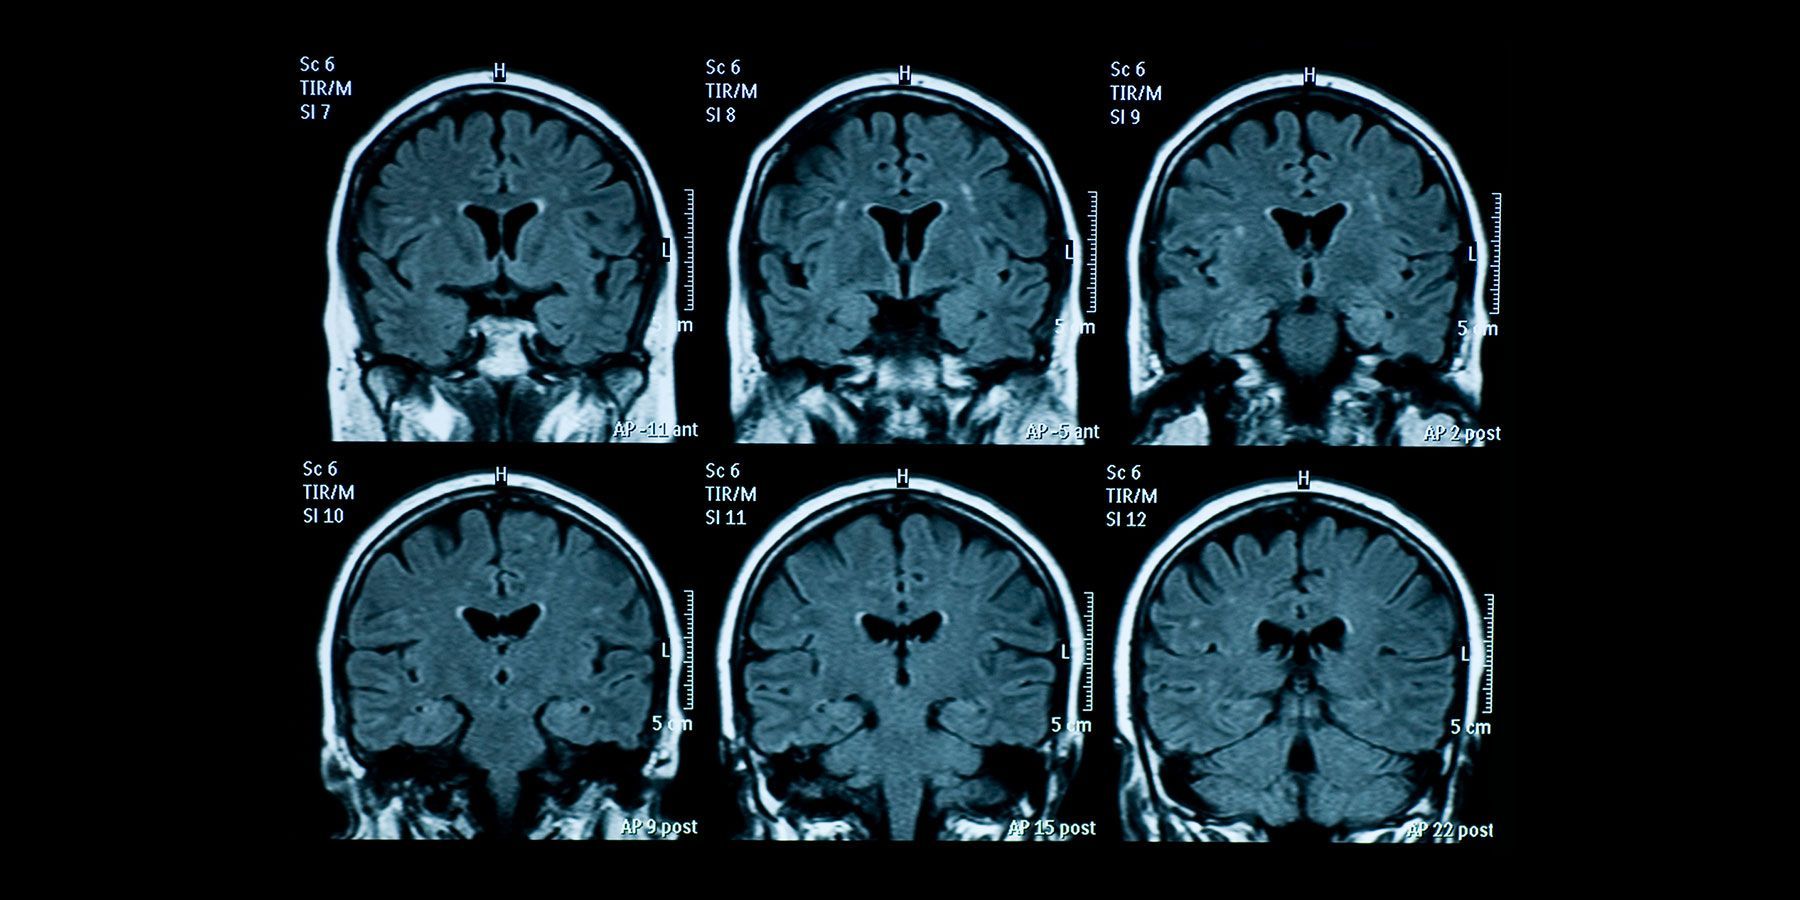

Comparison of genes and MRI results shows associations

SAN ANTONIO, TX — A new study implicates 160 genes in brain shrinkage seen on MRIs of 45,000 healthy adults. The shrinkage is in the cortex, the dimply outer layer of the brain that gives rise to thinking, awareness, and action, and largely consists of gray matter.

The study, published Sept. 22 in the journal Nature Communications, examined 34 regions of the cortex in a discovery group of 22,894 individuals, then confirmed the findings in a replication group of 22,635 individuals.